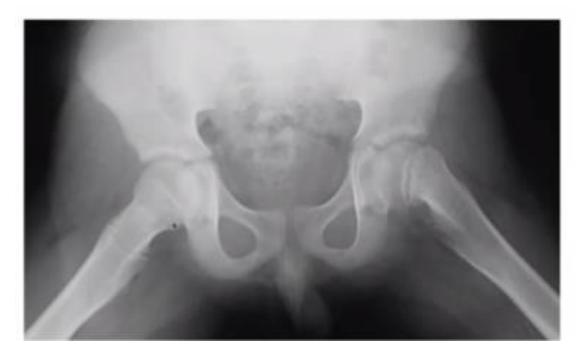

A 15-month-old child was brought to the clinic because of painless limping. There is no history of trauma. The pelvic x-ray is shown.

Q1: Write two abnormalities seen on the X-ray.

- Lateralization of the ossifying centre

- Acetabular angle more than 27ยฐ

- Broken Shenton line

- Shortening of the line from greater trochanter to the horizontal line

Q2: What is the most probable diagnosis?

- Developmental dysplasia of the hip (DDH)

10 months old child presenting with this condition:

- Right DDH